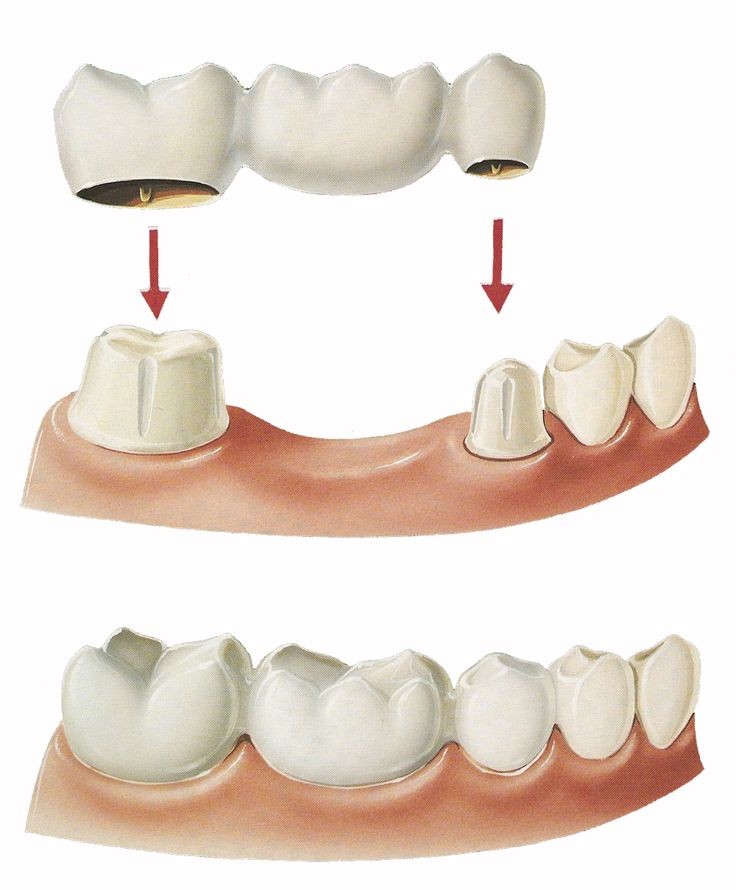

ما هو جسر الأسنان؟

هو قالب يتم تصميمه من مواد خاصة على شكل أسنان كاملة متصلة وذلك لملء بعض الأماكن الفارغة من الأسنان.

ويتم تثبيته عادة بربطه بطريقة خاصة بالأسنان الأصلية المجاورة له في الفك، وعادة ما يصنع من مواد، مثل: البورسلان ليحاكي مظهر الأسنان الطبيعية في الفم.

في هذا النوع يتم تصنيع قالب على هيئة سن واحد أو أكثر، ويتم تثبيته في المنطقة الفارغة من اللثة عبر ربطه بإحكام بالأسنان المجاورة من الجانبين والتي تسمى بالأسنان الداعمة.

خطوات تركيب الجسر

- تحضير الأسنان الطبيعية المحيطة بمنطقة جسر الأسنان لعملية تركيب الجسر، وهذا يتضمن برد الأسنان ووضع تيجان مؤقتة عليها ريثما يتم تصنيع التيجان الدائمة التي سوف تثبت الجسر في مكانه.

- تركيب الجسر مع التيجان السنية الجديدة المتصلة به وتثبيته في مكانه بمواد خاصة في الزيارة التالية، ثم يتأكد الطبيب من أن عضة المريض مناسبة وأن الأسنان ليست مرتفعة بالنسبة له.